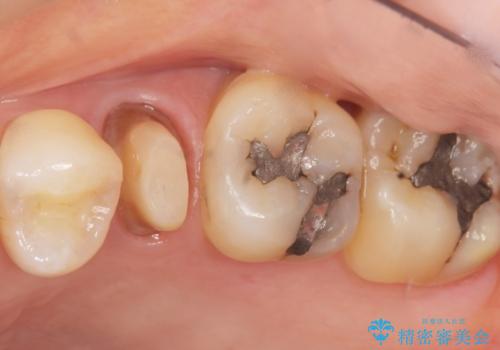

金属の詰め物と土台を除去し、ファイバーコア(金属を使わない強くてしなやかな土台)を植立したのちセラミッククラウンによる補綴治療を行いました。

精査したところ、右上の奥歯(右上5)に根尖病変を認めたため、こちらは根管治療後にセラミッククラウンによる補綴を行いました。